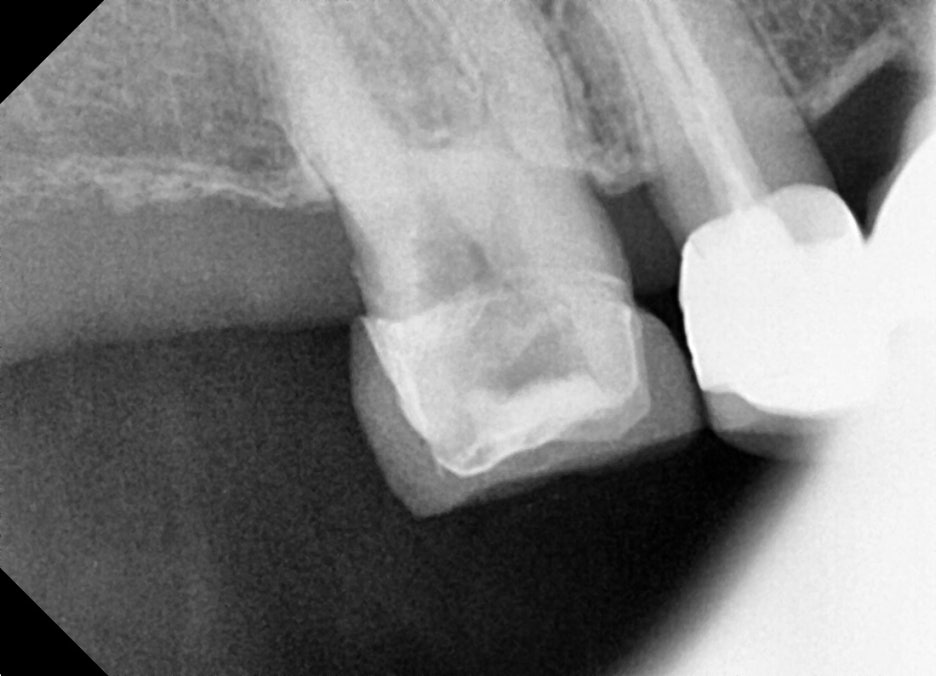

정밀 파악을 위해 추가로 치근단 엑스레이를 촬영했고, 실제로 치아 뿌리 끝까지 염증이 퍼져 있는 것이 확인되었습니다. 이 단계에서 신경치료 계획을 확정했습니다.

신경치료 1차

– 염증 제거 및 근관 확대

신경 치료는 치아의 표면을 파내서 속에 있는 염증을 제거하고, 보철물로 치아를 덮어씌우는 치료를 의미합니다.